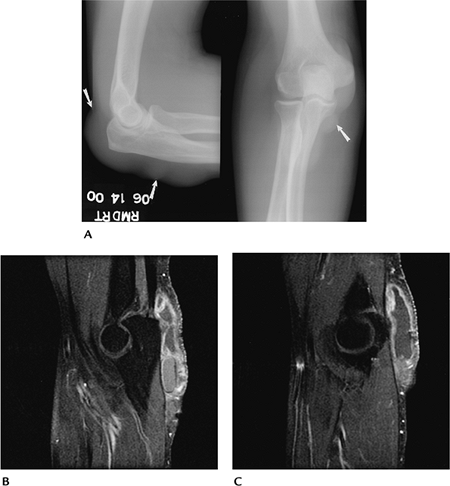

P.531

![]() |

FIGURE 8-14 Monteggia fracture. (A) Oblique radiograph showing an anterior dislocation of the radial head with a proximal ulnar fracture. Postreduction AP (B) and lateral (C) radiographs with internal fixation of the ulnar fracture.